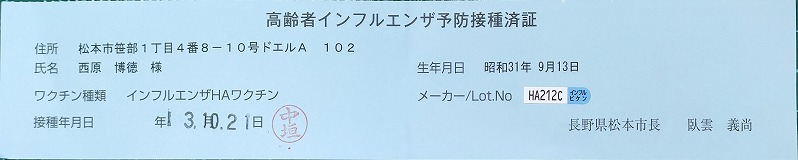

高齢者肺炎球菌予防接種済証.jpg)

高齢者肺炎球菌予防接種済証.jpg)